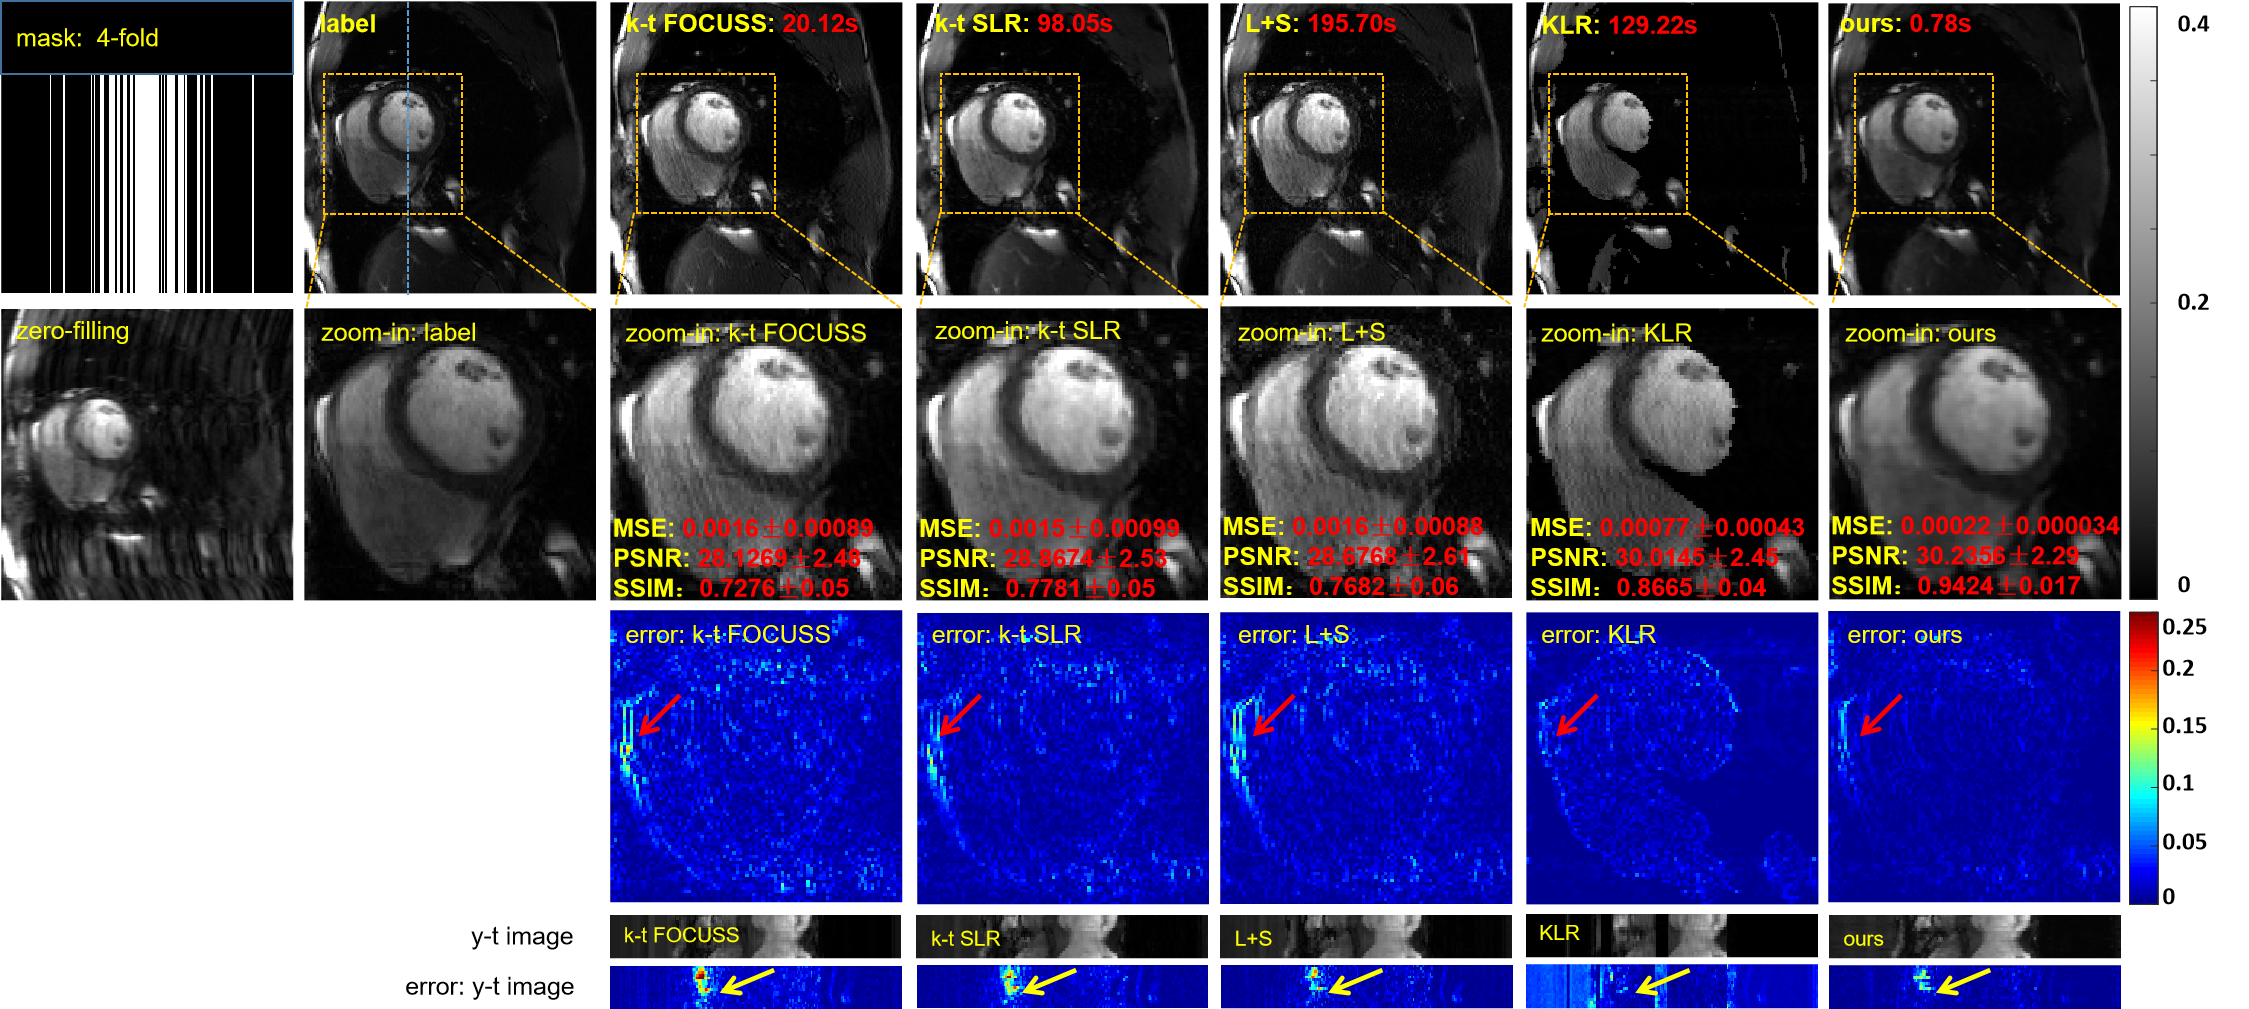

To demonstrate the efficacy of the proposed unsupervised learning method, we compared it with several state-of-the-art CS/LR methods including k-t FOCUSS [6], k-t SLR [11], L+S [10] and KLR [12]. We adjusted the parameters of the competing methods to elicit their best performance. A 1D random Gaussian mask was used for training and testing. The reconstruction results of these methods at 4-fold acceleration are shown in Fig.5. The reconstruction results of the four CS-based methods contain fewer structural details and more artifacts than do the reconstruction results of the proposed method. We also enlarged the cardiac region and its error map for demonstration to show that our method achieves the best reconstruction performance in the cardiac region, especially the details marked by the red arrow. The y-t image and its error map, which were extracted from the 124th slice along the y and temporal dimensions, also clearly illustrate the superior performance of the proposed method. The evaluation indexes, MSE, PSNR, and SSIM, can be found in the enlarged view of the heart regions. All the quantitative results shown are the averaged results on the test data set, and the standard deviations are also given. We observe that the MSE, PSNR and SSIM indexes of the proposed method are the best among all the methods. The red numbers represent the reconstruction time of these methods for the entire volume. Our method also has the shortest reconstruction time–hundreds of times shorter than those of the other methods.

The reconstruction results of the different methods at 8-fold acceleration are shown in Fig.6. At 8-fold acceleration, we can reach the same conclusion as with 4-fold acceleration.